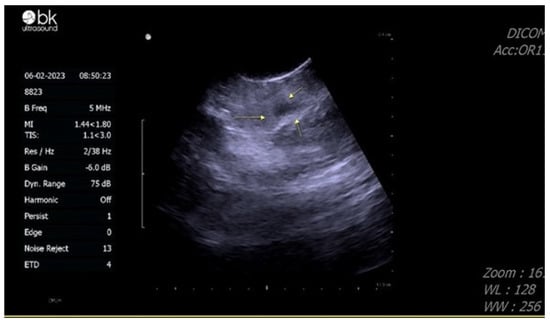

2. Case Presentation